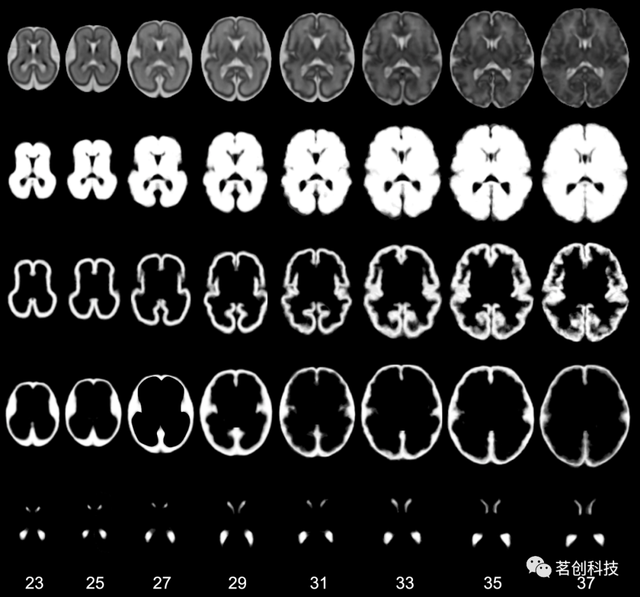

发育中大脑的动态4D概率图谱

这是一组矫正胎龄后的29-44周新生儿的概率图谱,由153名不同年龄的新生儿受试者细分而来。该图谱由平均T2加权强度模板和相应的组织概率图组成,具有动态生成结构的矫正尺寸和形状。该图谱提供了六种结构的组织概率图——皮层、白质、皮层下灰质、脑脊液、脑干和小脑。组织细分是基于皮层下灰质、脑干和小脑的分割,这是通过对三个典型图像的手动分割转换为其他图像得到的。

来源:A dynamic 4D probabilistic atlas of the developing brain.

发育中胎儿大脑的多通道4D概率图谱

这是一个由80名大脑正常发育的胎儿构建而成的时空图谱,扫描时胎龄在21.7到38.7周之间。可下载的图谱包括组平均的T2加权图像模板和脑膜、皮层、半球、脑脊液和脑室的组织概率图,适用于23到37周的胎儿。采用基于概率图谱先验的自动组织分割算法创建组织概率图。

来源:Construction of a consistent high-definition spatio-temporal atlas of the developing brain using adaptive kernel regression.